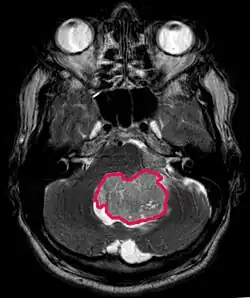

Das Medulloblastom ist der häufigste bösartige Hirntumor im Kindesalter. Die höchste Inzidenz tritt bei Kindern zwischen 2 und 7 Jahren auf. Das größte Krankheitsrisiko besteht weiterhin im Kindesalter, da ein Medulloblastom bei Menschen über 21 Jahre sehr selten ist.

Dieser Tumor ist typisch für die hintere Schädelgrube, wo er in beiden Hemisphären des Kleinhirns oder im Kleinhirnwurm lokalisiert ist. Da er invasiv ist und schnell wächst, breitet er sich normalerweise über den Liquor auf andere Teile des Zentralnervensystems (ZNS) aus und kann den Boden des nahegelegenen vierten Ventrikels und die Hirnhäute infiltrieren. Seltener kann es zu zusätzlichen ZNS-Metastasen kommen. Bei Auftreten der Malignität zählen Gleichgewichtsverlust, mangelnde Koordination, Diplopie, Dysarthrie und aufgrund der Beteiligung des vierten Ventrikels, bei dem häufig ein obstruktiver Hydrozephalus auftritt, Kopfschmerzen, Übelkeit und Erbrechen sowie ein instabiler Gang zu den Symptomen.

Das Kernspintomogramm zeigt normalerweise eine massive Kontrastverstärkungsläsion, an der das Kleinhirn beteiligt ist. Wie oben erwähnt, hat das Medulloblastom eine hohe Neigung, die Leptomeninges lokal zu infiltrieren sowie sich durch den Subarachnoidalraum auszubreiten, und bezieht dabei die Ventrikel, die zerebrale Konvexität und die leptomeningealen Oberflächen der Wirbelsäule mit ein. Folglich ist es notwendig, die gesamte kraniospinale Achse in Resonanz zu bringen.